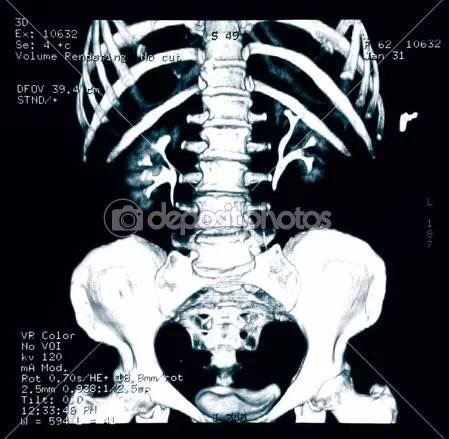

根據(jù)美國放射協(xié)會和婦產(chǎn)協(xié)會的數(shù)據(jù),孕婦接受單次胸部x線檢查腹中胎兒受到的照射劑量為0.02–0.07毫rad。記住,高于5000毫rad才會造成胎兒損傷。單次腹部x線平片胎兒受到的照射量為100毫rad,腎盂靜脈造影胎兒受到的照射量可能大于1rad。乳腺鉬靶檢查胎兒受到的照射量為7-20毫rad。鋇灌腸或者小腸連續(xù)成像檢查胎兒受到的照射量可以達到2-4rad。頭胸部CT檢查胎兒受到的照射量小于1rad。腹部或者腰椎CT掃描胎兒受到的照射可以達到3.5rad。

也就是說,普通x線平片通常只會暴露胎兒于非常小的照射劑量。而且通常孕期需要做x線檢查時候,孕婦的腹部是會用含有鉛的防護衣保護起來的,更進一步降低受照劑量。除開鋇灌腸和小腸連續(xù)成像,絕大多數(shù)造影劑熒光檢查也只會給胎兒帶來毫rad的劑量。CT造成的照射依照射數(shù)量和成片距離會有不同。盆腔CT可能會給胎兒帶來高達1.5rad的照射,但放射科醫(yī)生通過使用低劑量技能是可以將它降低到接近250毫rad的。